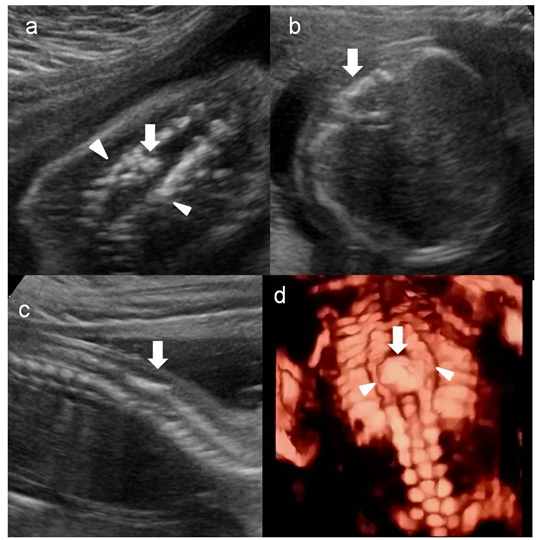

Figure 1 Ultrasonography of the fetal spine: coronal (A), axial (B), sagittal (C) sections and 3D (D) reconstruction: Note the posterior hyperechogenic focus (thick arrow) seen within widened spinal canal (between arrow heads).